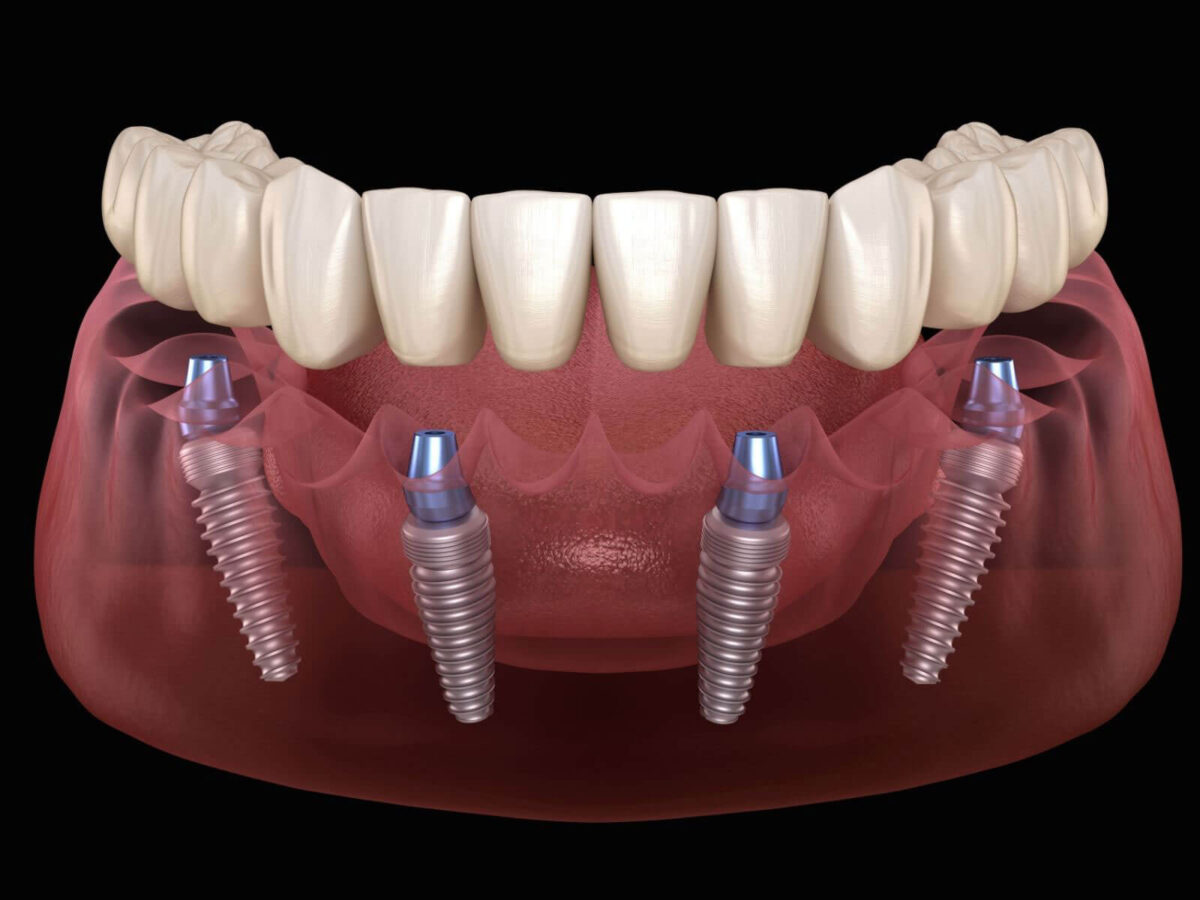

What An Implant Actually Does

A dental implant is a metal post that is fixed into the jaw. It goes into the space where the tooth root once sat. A crown or a bridge is added on top later. The post holds everything in place. It keeps the tooth steady and gives the bone something solid to stay around. That part makes the difference. Bridges lean on nearby teeth. Dentures sit on the gums. Implants do neither. They settle into the jaw itself. Over time, the mouth treats it as part of the structure. That is usually when people start asking, “Are dental implants worth it?”